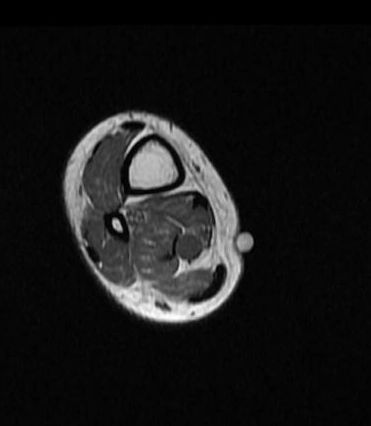

U vỏ bao thần kinh ngoại biên (Peripheral Nerve Sheath Tumors)